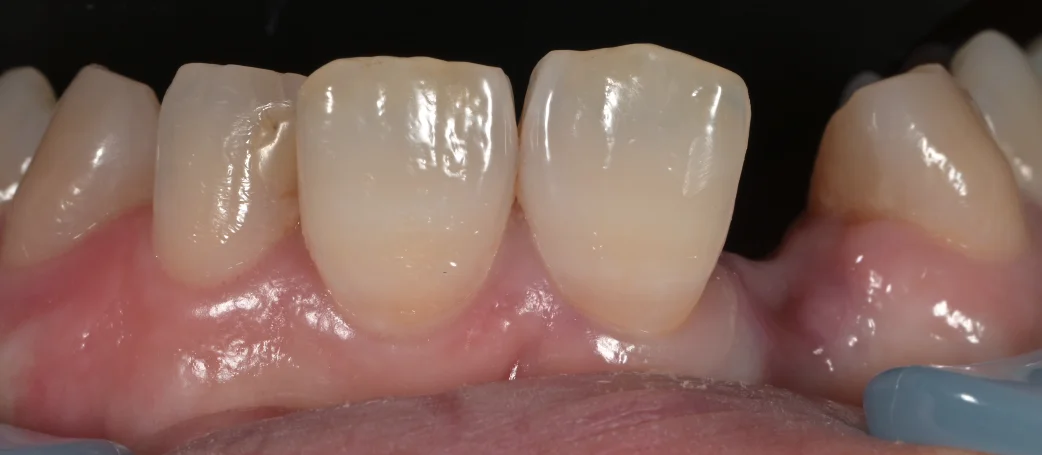

まずは術前の口腔内写真です。

では今回どのように治療したのかというと・・・術後の写真がこちらになります。

こんな感じです。

元の歯はぱっと見ほとんど変わってないように見えますよね?